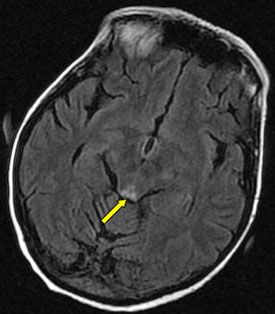

A 54-year-old woman was admitted to the hospital with a chief complaint of altered mental status and confusion of 2 days’ duration. She had a 2-week history of increased swelling in both legs and difficulty in walking. There was no reported vomiting, dyspnea, or increasing pain. She had been receiving chemotherapy for 5 months to treat metastatic pancreatic adenocarcinoma. Other relevant medical history included deep venous thrombosis, anemia, chronic hyponatremia, osteoporosis, irritable bowel syndrome, and seasonal allergies. Cranial nerve function was intact but ocular examination revealed bilateral horizontal nystagmus. Neuromuscular examination revealed bilateral lower extremity 4/5 strength with inability to stand or walk. MRI study of the brain revealed abnormal signaling in the periaqueductal gray matter.